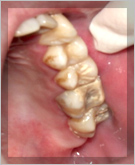

歯周病の直接的な原因は歯垢(プラーク)です。

歯垢はバイオフィルムともいい、細菌の塊です。

このプラークが体液中のカルシウムを取り込んで石灰化していくと歯石となります。

歯石自体が感染源となる事はありませんが、プラークの温床となってしまいます。

歯周病治療の基本はこの歯垢を徹底的に除去することから始めていきます。